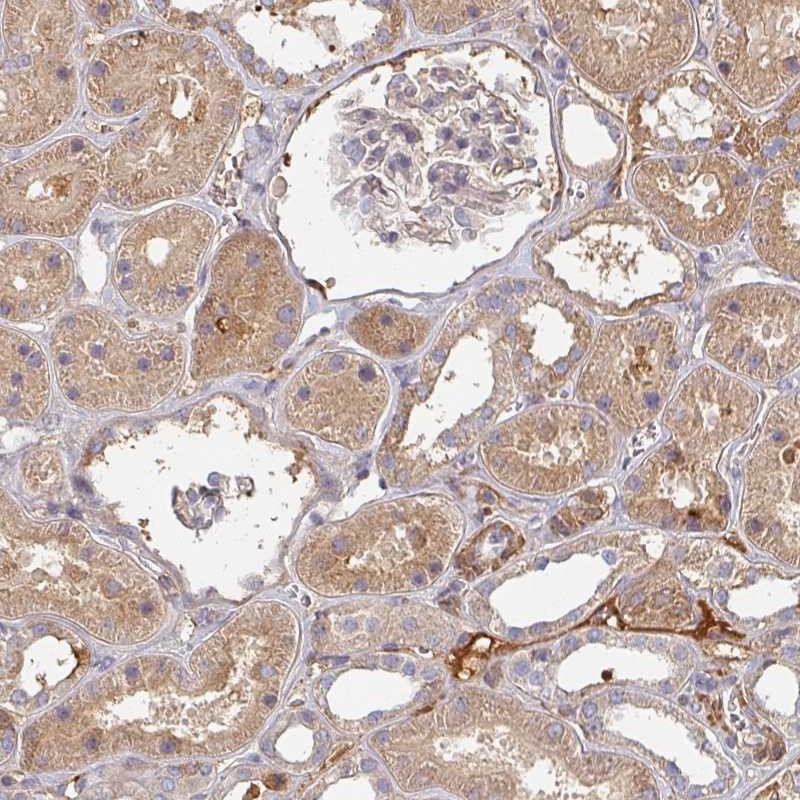

Immunohistochemical staining of human kidney shows moderate cytoplasmic positivity in renal tubules.